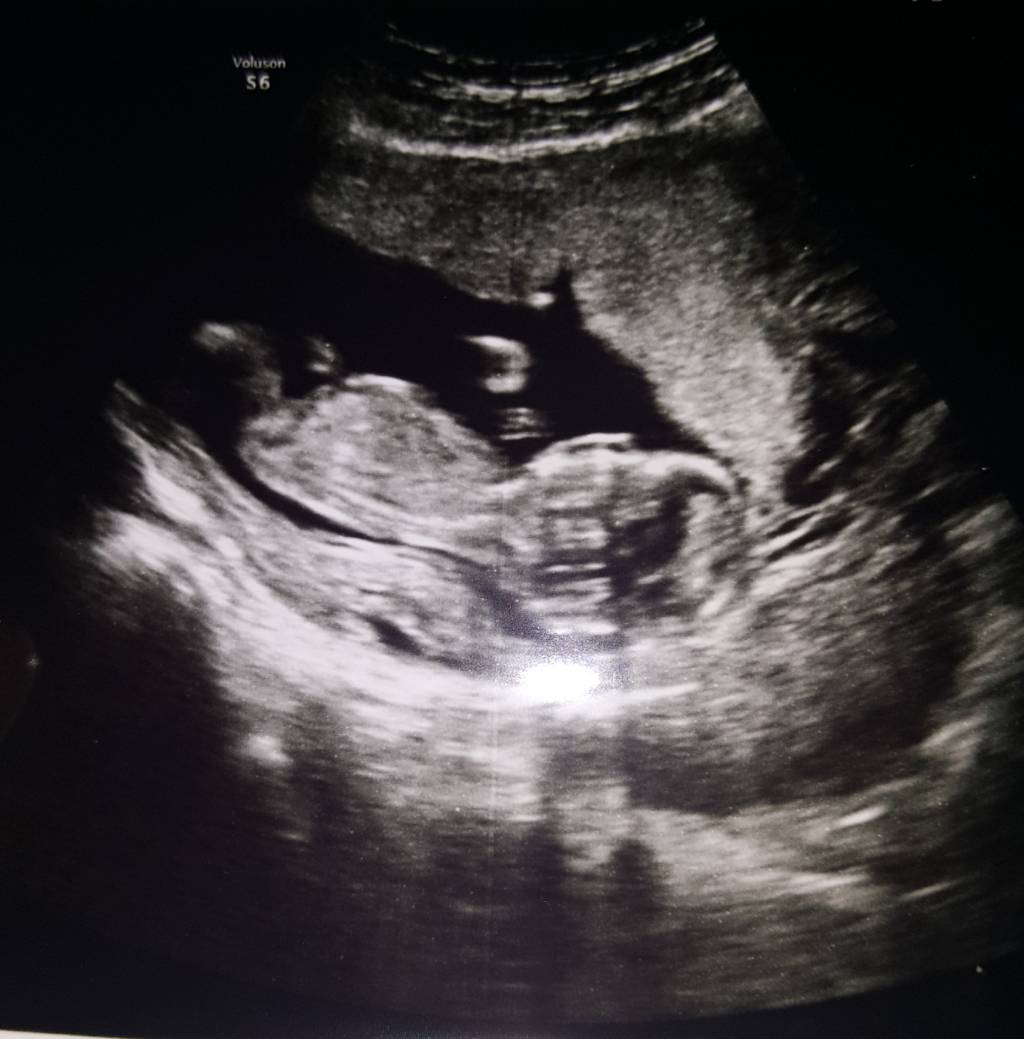

My też już po badaniu. Maleństwo caly czas ospałe i leniwe. Lekarz go stale budził. Wielkość ponad 7 cm. Według usg dziecko jest tydzien starsze. Wszystkie wyniki bardzo dobre. Ryzyko bardzo niskie. Płeć nieznana [emoji3]Zobacz załącznik 920425